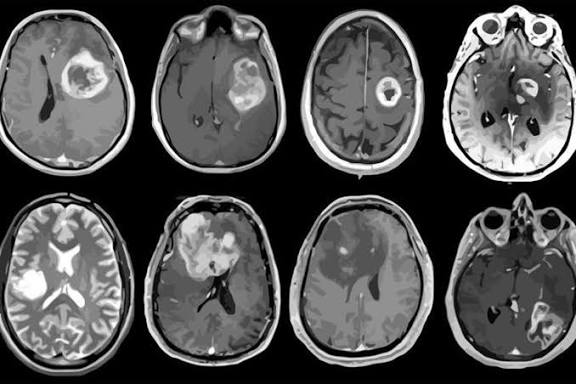

Los investigadores probaron un nuevo tratamiento experimental contra el glioblastoma, uno de los cánceres cerebrales más agresivos y difíciles de tratar, obteniendo resultados sin precedentes.

En el caso más sorprendente, una mujer de 57 años vio cómo su tumor casi desaparecía en tan solo cinco días tras recibir la nueva terapia. Otro paciente presentó una reducción del 60 % en el tamaño del tumor en poco más de dos meses.

Aunque los tumores reaparecieron posteriormente, los científicos consideran que estos resultados representan un avance crucial en la búsqueda de tratamientos más eficaces y duraderos.